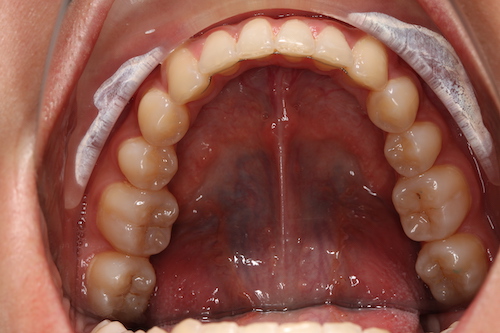

После